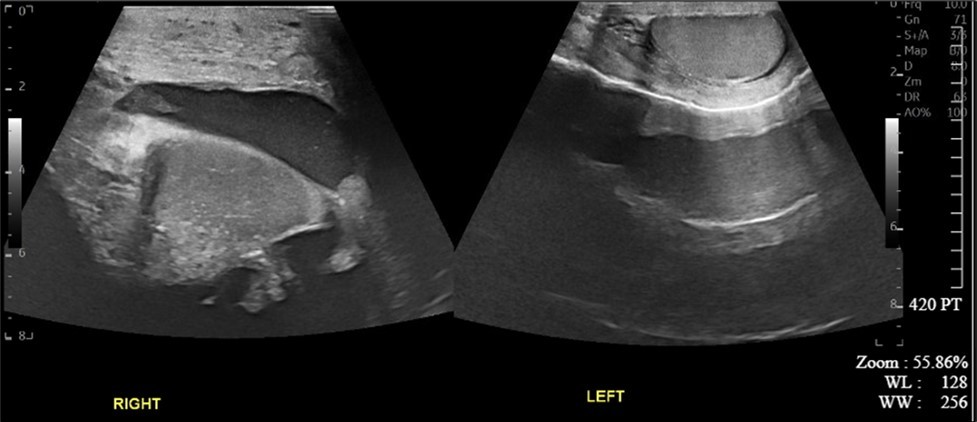

A 34-year-old male presented to the Emergency Department with complaints of large right-sided scrotal swelling, accompanied by scrotal discomfort. The patient’s past medical history was remarkable for a right-sided inguinal hernia, which had been present for several years and was repaired via right open herniorrhaphy with mesh placement three months prior. Physical examination prior to the herniorrhaphy revealed a large inguinoscrotal swelling, measuring 5 inches by 6 inches. During the herniorrhaphy, a very large hernia sac was encountered that could not be fully dissected from the cord structures and required placement of two large meshes; however, the testicles were successfully reduced back into the scrotum. Ultrasound of the right testicle revealed a large hypoechoic space with a complex collection and posterior displacement of the testicle, indicating a possible hydrocele (Figure 1, Figure 2, Figure 3, Figure 4). The patient was taken to the operating room for a right hydrocelectomy. During the procedure, it was noted that the penis was buried within the scrotal swelling, necessitating the placement of a Foley catheter to identify surrounding structures. Upon incision through the Dartos fascia, significant fibrotic tissue and fluid were encountered, making it difficult to maneuver around the hydrocele sac. Upon incising the hydrocele sac, a large collection of thick, dark brown fluid resembling old blood clots was immediately aspirated. Approximately 2 liters of fluid were drained from the sac. After identifying the testicle and cord structures, the proper placement of the testicle within the scrotum was verified. Due to excessive scrotal skin, a scrotoplasty was performed prior to suturing the scrotal skin and fascia (Figure 5). The postoperative hospital course was unremarkable. The patient was discharged with plans to return to the clinic for follow-up with the surgeon.

Figure 1.Ultrasound imaging of right and left testicles in the transverse plane.